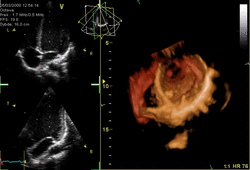

Several imaging methods can be used to assess the anatomy and function of the heart, including ultrasound (echocardiography), angiography, CT, MRI, and PET, scans. An echocardiogram is an ultrasound of the heart used to measure the heart's function, assess for valve disease, and look for any abnormalities. Echocardiography can be conducted by a probe on the chest (transthoracic), or by a probe in the esophagus (transesophageal). A typical echocardiography report will include information about the width of the valves noting any stenosis, whether there is any backflow of blood (regurgitation) and information about the blood volumes at the end of systole and diastole, including an ejection fraction, which describes how much blood is ejected from the left and right ventricles after systole. Ejection fraction can then be obtained by dividing the volume ejected by the heart (stroke volume) by the volume of the filled heart (end-diastolic volume).[85] Echocardiograms can also be conducted under circumstances when the body is more stressed, in order to examine for signs of lack of blood supply. This cardiac stress test involves either direct exercise, or where this is not possible, injection of a drug such as dobutamine.[77]